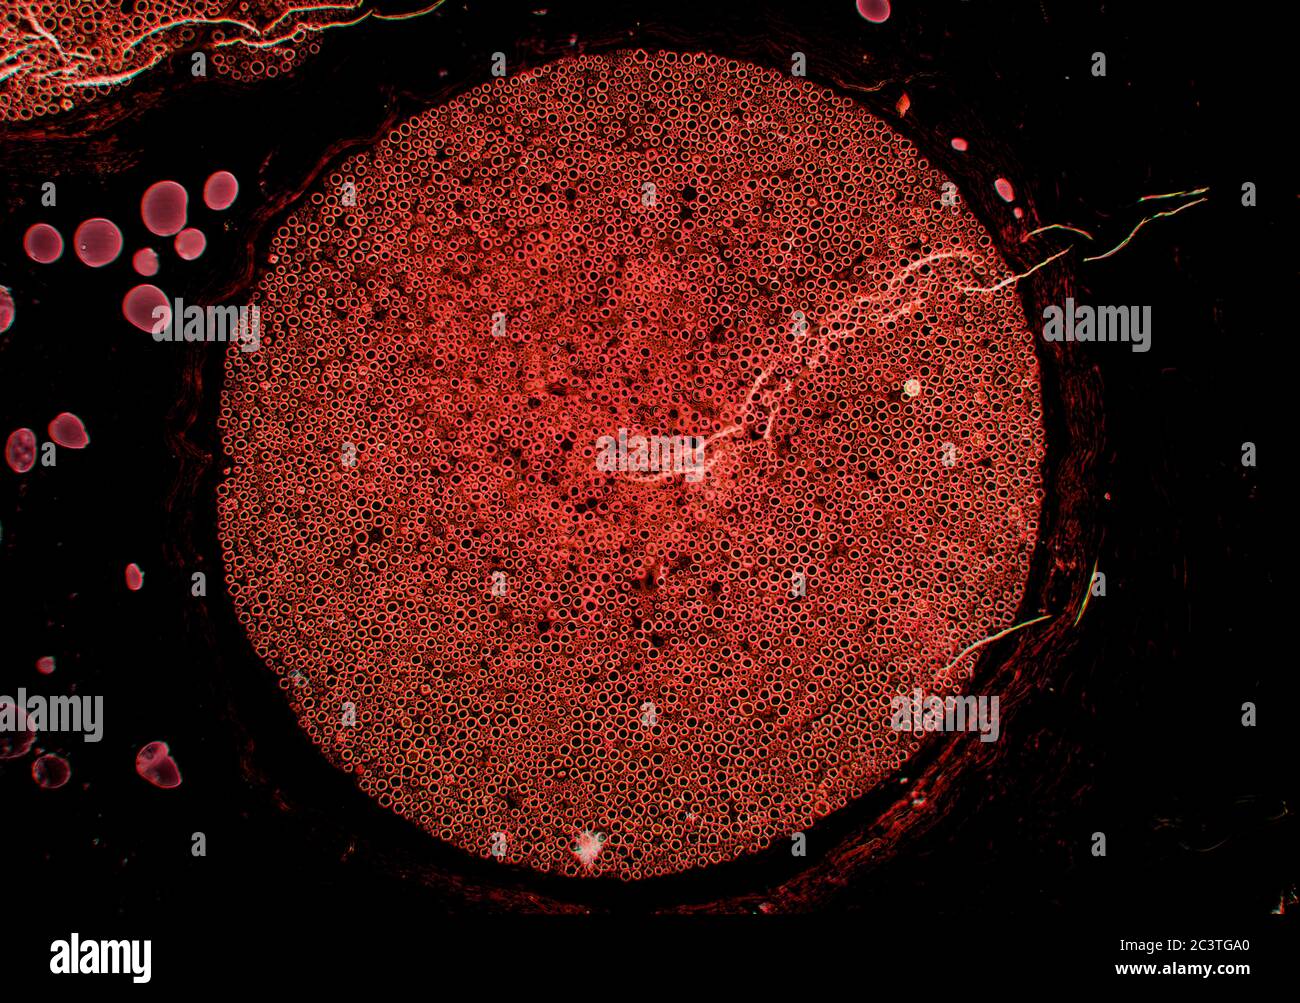

Nerf sciatique de mammifère, coupe transversale, vue au microscope Banque D'Imageshttps://www.alamyimages.fr/image-license-details/?v=1https://www.alamyimages.fr/nerf-sciatique-de-mammifere-coupe-transversale-vue-au-microscope-image363801368.html

Nerf sciatique de mammifère, coupe transversale, vue au microscope Banque D'Imageshttps://www.alamyimages.fr/image-license-details/?v=1https://www.alamyimages.fr/nerf-sciatique-de-mammifere-coupe-transversale-vue-au-microscope-image363801368.htmlRM2C3TGA0–Nerf sciatique de mammifère, coupe transversale, vue au microscope